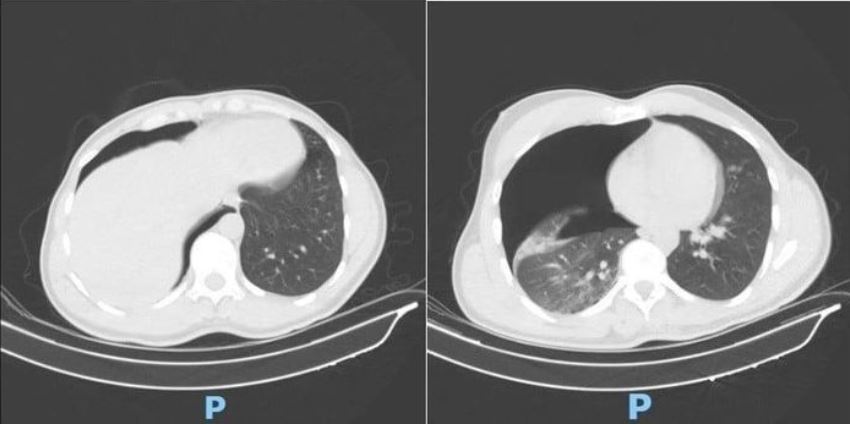

Phim CT Scan lồng ngực sáng ngày nhập viện ghi nhận bệnh nhân bị tràn khí

màng phổi phải lượng nhiều. Ảnh: BVCC.

Nhận định đây là ca bệnh nặng, ê-kíp trực lập tức kích hoạt quy trình cấp cứu khẩn cấp. Bác sĩ Phạm Ngọc Huy, khoa Điều trị theo yêu cầu - Y học thể thao, cho biết kết quả chụp CT scan lồng ngực - mạch máu ghi nhận bệnh nhân bị tràn khí màng phổi phải lượng nhiều, chèn ép phổi gây khó thở. Ngoài ra, bệnh nhân bị gãy cung bên các xương sườn số 2, 3, 4 bên phải, gãy phức tạp 1/3 giữa xương đòn phải, di lệch nhiều và có mảnh rời.